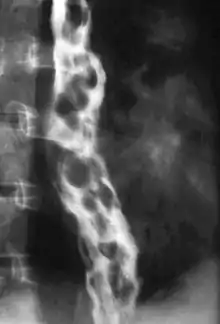

Dilated submucosal veins are the most prominent histologic feature of esophageal varices. The expansion of the submucosa leads to elevation of the mucosa above the surrounding tissue, which is apparent during endoscopy and is a key diagnostic feature. Evidence of recent variceal hemorrhage includes necrosis and ulceration of the mucosa. Evidence of past variceal hemorrhage includes inflammation and venous thrombosis.

Therapeutic endoscopy is considered the mainstay of urgent treatment. The two main therapeutic approaches are variceal ligation (banding) and sclerotherapy.